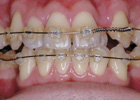

歯を抜かずに治療ができた例

治療前

治療後

歯を抜いて治療した例 その1

治療途中

歯を抜いて治療した例 その2